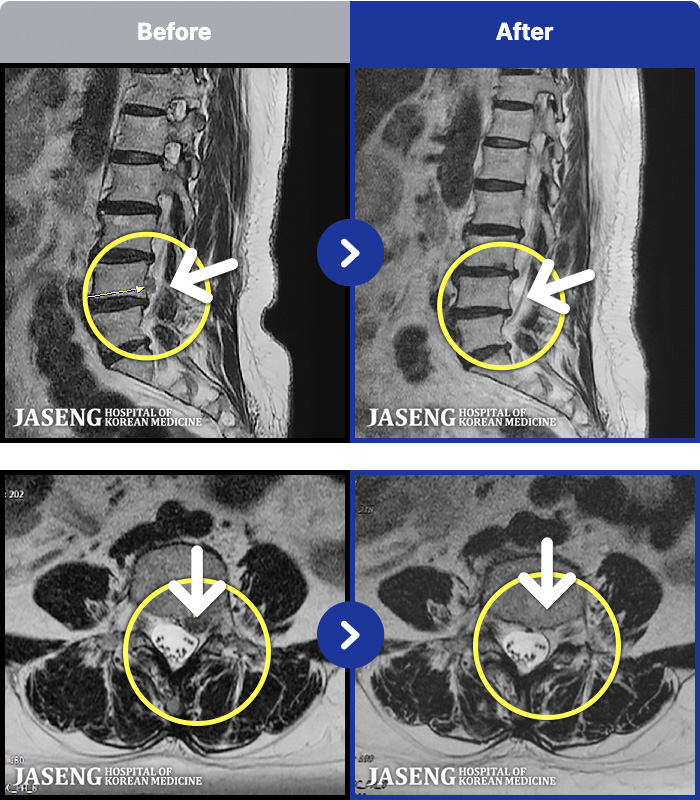

1,240 MRI ũ ʸ Ȯϼ.

MRI ġ

㸮 ϻ .